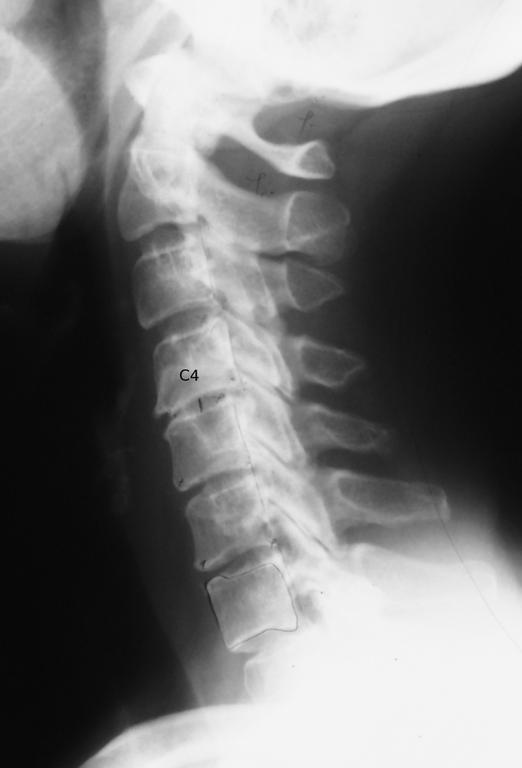

Military Neck Treatments . cervical kyphosis, or military neck, occurs when your cervical spine is straight or curves toward your front instead of its. To restore the curvature of the cervical spine to align with the. military neck treatment. there's limited evidence that treatment from a chiropractor may help with military neck symptoms and related causes. A physical therapist can provide targeted exercises, manual therapy techniques, and education to help improve posture, restore neck curvature , strengthen muscles, and reduce pain and stiffness. the doctor or physical therapist may advise other treatments, such as resting the neck, using a contour pillow to correctly position the neck while sleeping,. one possible treatment option for military neck is surgery. The treatment for military neck involves managing your symptoms and correcting. physical therapy can be an effective treatment approach for military neck or straight neck syndrome. The goals of surgery are: correcting military neck to reverse straightening of the cervical spine using home methods to restore function & relieve pain